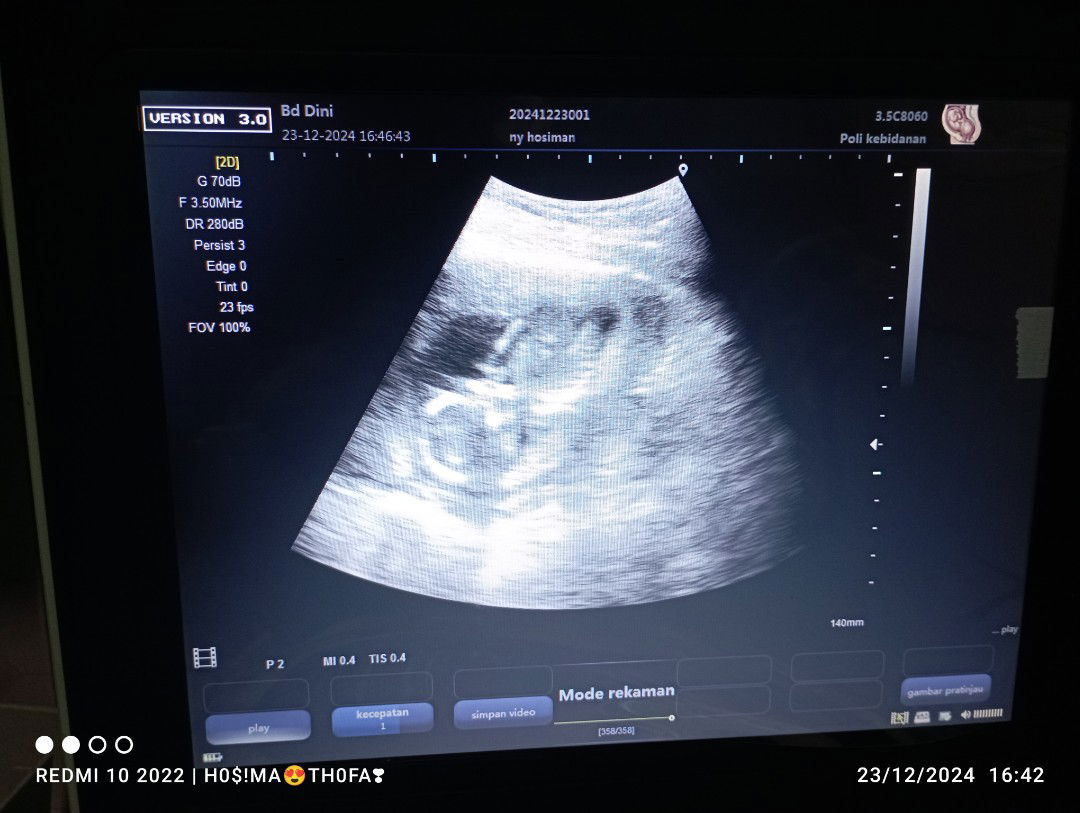

tapi setiap saya periksa usg ke bidan slalu yg di kasih cuman itu saja bun